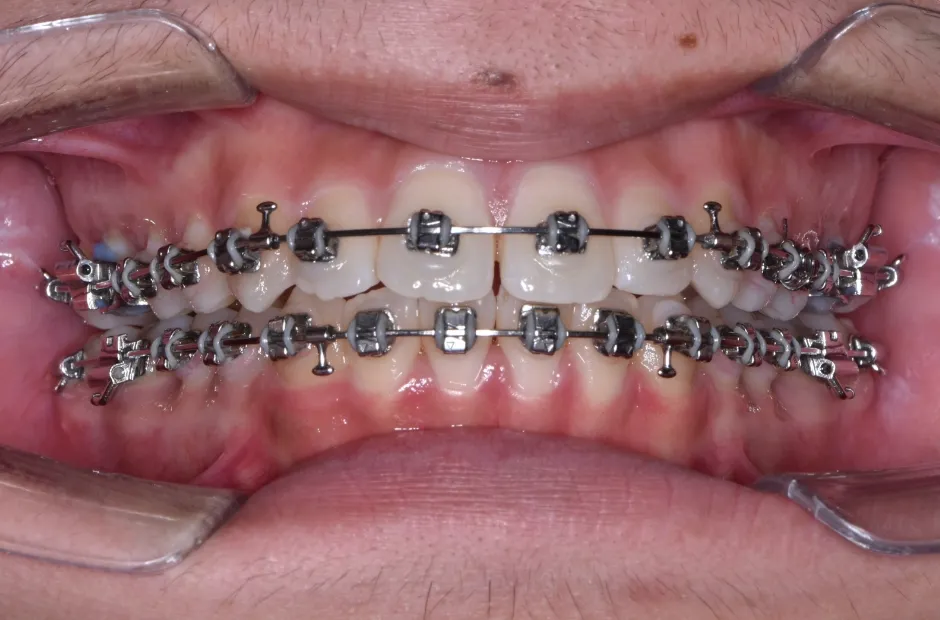

治療中

叢生

| 診断名・主訴 | 叢生 |

| 年齢・性別 | 43歳・女性 |

| 治療期間・回数 | 2年7か月 27回 |

| 治療に用いた主な装置 | 舌側矯正 |

| 抜歯部位 | 両顎4,4 |

| 治療費 | 100万円(税抜) |

| リスク・副作用 | 装置による違和感・疼痛・歯肉退縮・歯根吸収・虫歯のリスクなど |